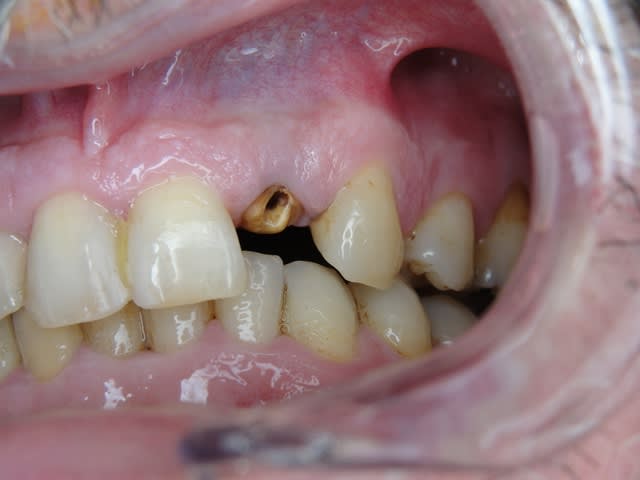

J´ai mis des photos pour mieux voir....

Merci pour ta remarque.C´est vrai que cela est mieux si on ne prérare pas ou presque pas les prep cap à cause des shippings . Normalement je ne les prépare pas, je choisis une forme (avec angle et longueur diiférents) selon le cas et ensuite je les cémente.

Photo 2 du dernier cas, je crains beaucoup pour la plaque d'os en vestibulaire, même en flapless.